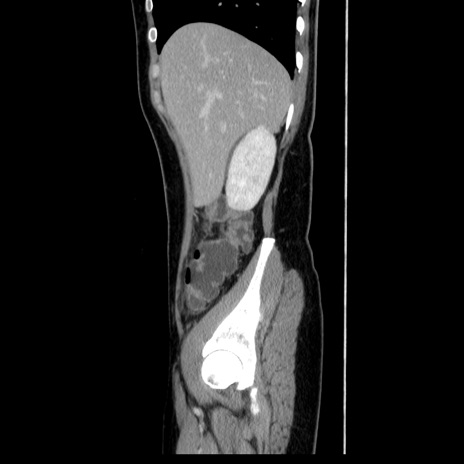

症例39(矢状断像)

【症例】40歳代女性

【主訴】上下腹部痛

【現病歴】2日目から下腹部痛あり。夜間は痛みで眠れなかった。昨日より上腹部痛と下痢が出現。臥位で痛みは軽快したため、休んでいた。本日になって臥位でも立位でも痛みが強くなってきたため救急要請。

【既往歴】子宮内膜症

【身体所見】部:平坦・軟、左上下腹部に圧痛あり、反跳痛あり。

【データ】WBC 21800、CRP 26.78

CT